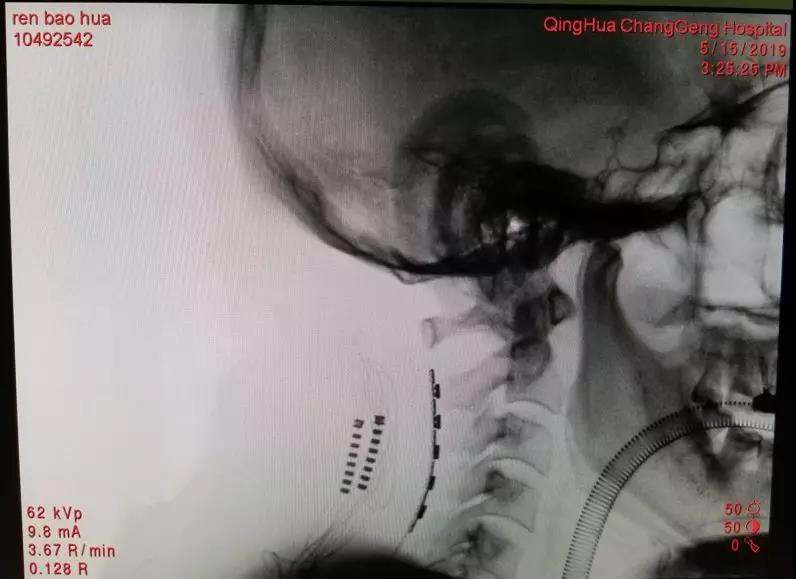

2019年5月15日,王劲副院长主刀手术,于颈椎硬膜外植入片状电极,利用电刺激阻断疼痛信号的传导,微小的电极片上有3排总计16个触点,确保术后能精准调控,术中予以刺激同时联合神经电生理监测,客观判断疼痛区域可以被电刺激所覆盖,最后使用O形臂确认电极精准植入颈椎硬膜外腔。术后经过近一周的刺激测试,患者左上肢疼痛改善率达60%以上,术前因为疼痛难以入眠,术后每晚可以自然入睡6小时。按照临床试验方案,任先生继续接受植入了皮下电脉冲发射器。

O形臂确认电极位置